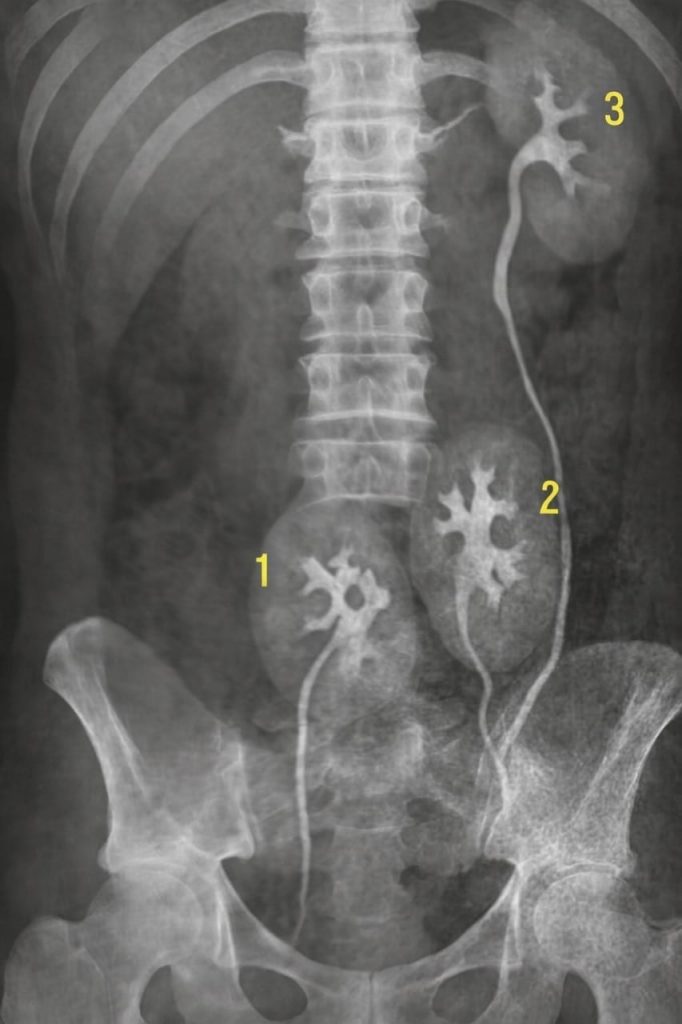

Tři ledviny.

Tři.

Všechny plně funkční. Všechny přirozeně vytvořené.

Jedna navíc — tichý společník od narození. Nežádala o pozornost. Nikdy nebolela. Nikdy nedala signál, že existuje. Prostě tam byla. Jako svědek každého dne, každého rozhodnutí, každé chyby i radosti.